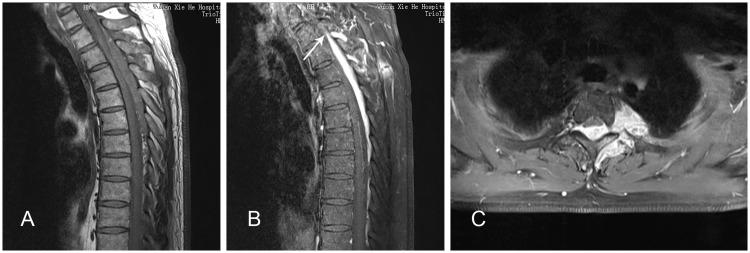

Rosai-Dorfman disease (RDD) or sinus histiocytosis with massive lymphadenopathy is a rare benign disorder usually characterized by massive painless cervical lymphadenopathy and systemic manifestations. Extranodal involvement, especially spinal involvement, is extremely rare. We report a 41-year-old man who presented with only intermittent dorsodynia. His condition was diagnosed as non-specific inflammatory disease on the basis of preoperative puncture biopsy results. We performed total surgical resection. Histopathological findings showed distinctive emperipolesis and immunohistochemistry results were positive for cluster of differentiation CD68 and S100 and negative for CD1a. A good prognosis was confirmed at the 3-month follow-up visit. This is the first case of RDD of the subdural spine with such a long segment lesion. There is still no consensus regarding appropriate therapy for this type of RDD and the preoperative diagnosis remains challenging. The unusual presentation of our case serves as a reference when diagnosing and treating RDD.

罗萨伊-多夫曼病(RDD)或伴有巨大淋巴结病的窦性组织细胞增生症是一种罕见的良性疾病,通常表现为无痛性巨大颈部淋巴结病和全身症状。结外受累,尤其是脊柱受累极为罕见。我们报告一名41岁男性,仅表现为间歇性背痛。根据术前穿刺活检结果,其病情被诊断为非特异性炎症性疾病。我们进行了全手术切除。组织病理学检查结果显示有独特的血细胞吞噬现象,免疫组化结果显示分化簇CD68和S100呈阳性,CD1a呈阴性。在3个月的随访中证实预后良好。这是首例硬膜下脊柱RDD伴如此长节段病变的病例。对于这类RDD的适当治疗仍未达成共识,术前诊断仍然具有挑战性。我们病例的不寻常表现为RDD的诊断和治疗提供了参考。